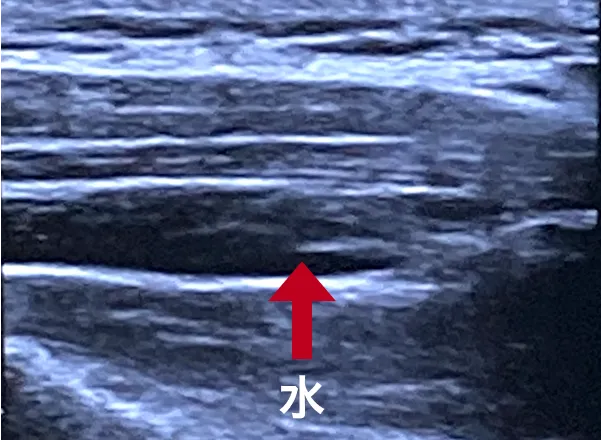

薬剤を注入し、筋膜の癒着を改善

エコーで正確にトリガーポイントを見ながら、生理用食塩水を注射し、癒着している筋膜を剥がします。筋膜が剥がれていく様子を、モニターで見ていただくことも可能です。

筋膜に水が入り、剥がれた状態

(赤矢印でさした黒い部分が水)